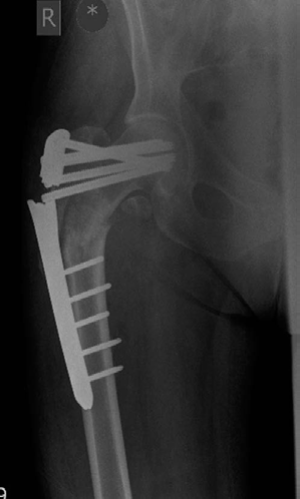

The implant has been under constant biomechanical load, which has led to the fatigue failure of the implant. In this particular design there is a stress riser at the junction of the last proximal locking hole and the tapered part of the plate, which dictates the failure point in the implant. In addition, the plating device is applied on the lateral aspect of the femur increasing the lever arm for the moment of force as compared with a cephalomedullary device, which further puts the fixed-angle

Figure 8.11 Anteroposterior (AP) radiograph right femur demonstrating hardware failure, 4 months postoperative.

plating device in this position at a biomechanical disadvantage. Similar results were reported with the use of compression hip screw and 95o plate.2 In this type of fracture an intramedullary device has better results and biomechanical stability.